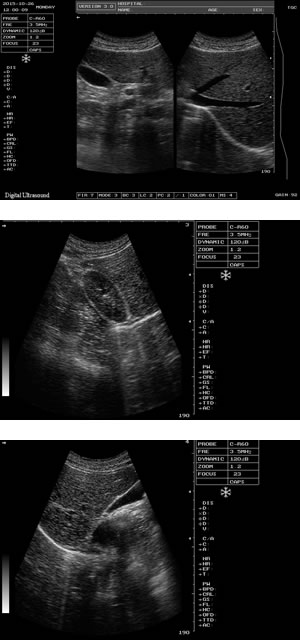

● 全新一代全數(shù)字筆記本式診斷儀器